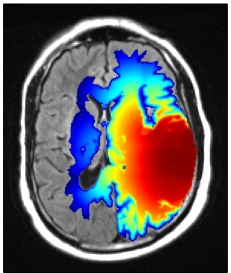

Refer to caption

Figure 8: Multifocal GBM located in the left temporal and frontal lobe: (a) coronal T1 post contrast image; (b) axial T1 post contrast image. The manually drawn CTV is shown in green, the model derived CTV in red.

A.1 Multifocal temporal/frontal lobe case

Figure 8 shows a multifocal GBM case involving the left temporal lobe as well as the frontal lobe. Figure 8a shows the coronal T1 post contrast image, revealing the contrast enhancing tumor mass in the temporal lobe. The axial T1 post contrast image in figure 8b shows the lesion in the frontal lobe. The simulated tumor cell density in figure 9a illustrates several features discussed in sections 3 and 4: The tumor growth model describes the steep fall-off of the tumor cell density in gray matter, leading to differences in the target volume around the lateral sulcus (figure 8b). In addition, modeling tumor cell infiltration through the corpus callosum leads to differences in the target volume in the contralateral frontal lobe. Figure 9 shows the IMRT plan comparison for a homogeneous 60 Gy prescription to the manual CTV (c) and the model-derived CTV (b). The figure shows that the differences in the target volume partly translate into differences in the dose distribution. In particular, the dose difference plot in figure 9d shows a lower dose in the lateral sulcus region for the model-based plan, and a higher dose in the contralateral hemisphere close to the corpus callosum.